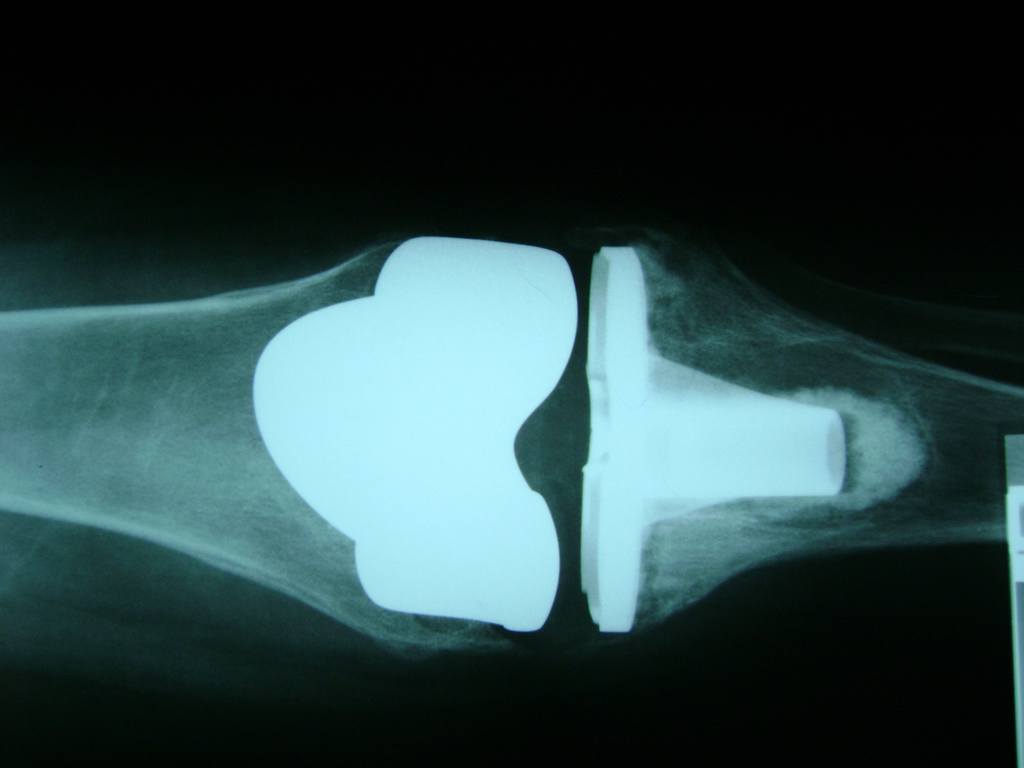

Cirugías de Codos - Rodilla

La artroscopia de rodilla es un cirugía en el cual la estructura interna de la articulación es examinada ya sea para realizar un diagnostico o para realizar un tratamiento, este procedimiento se realiza utilizando un instrumento parecido a un pequeño tubo llamado artroscopio.